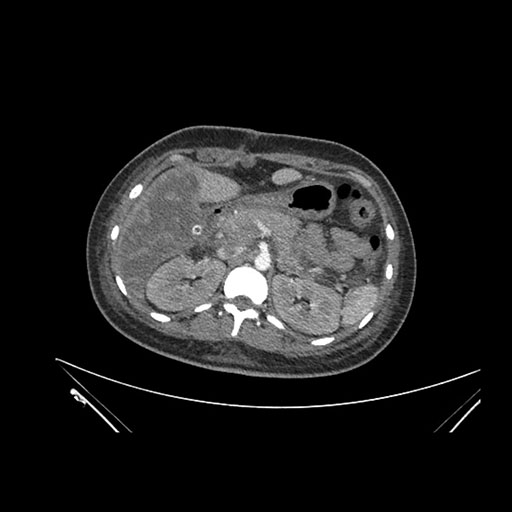

Imaging Analysis

Look through the patient's CT scan to identify any areas of concern for the necessary procedure.

Coronal Venous

Based on initial findings, which issue(s) would you be most concerned about?